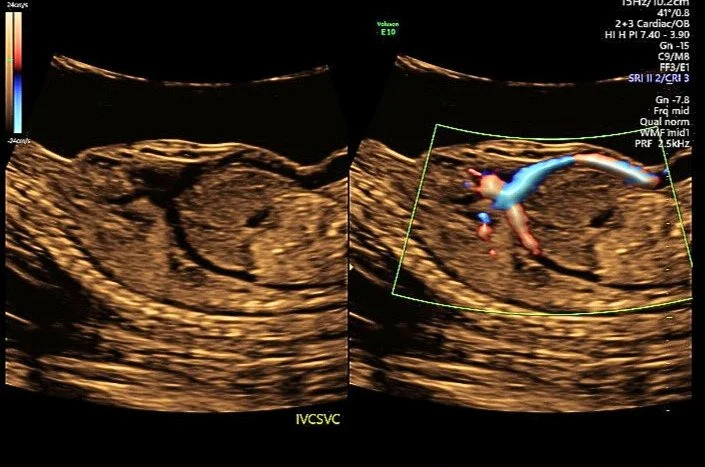

Absent Ductus Venosus

A patient was referred for a detailed anatomy survey due to Advanced Maternal Age. Upon ultrasound examination, ascites was initially suspected, but Doppler imaging revealed unexpected blood flow. Further evaluation confirmed an absent ductus venosus with the umbilical vein draining directly into the right atrium.

Additional findings included a single umbilical artery, persistent left superior vena cava, an apically offset mitral valve relative to the tricuspid valve, a duplicated right renal artery, and velamentous cord insertion. Due to the umbilical vein’s direct drainage into the right atrium, the perinatologist noted an increased risk for congestive heart failure. These findings were also associated with Noonan Syndrome.